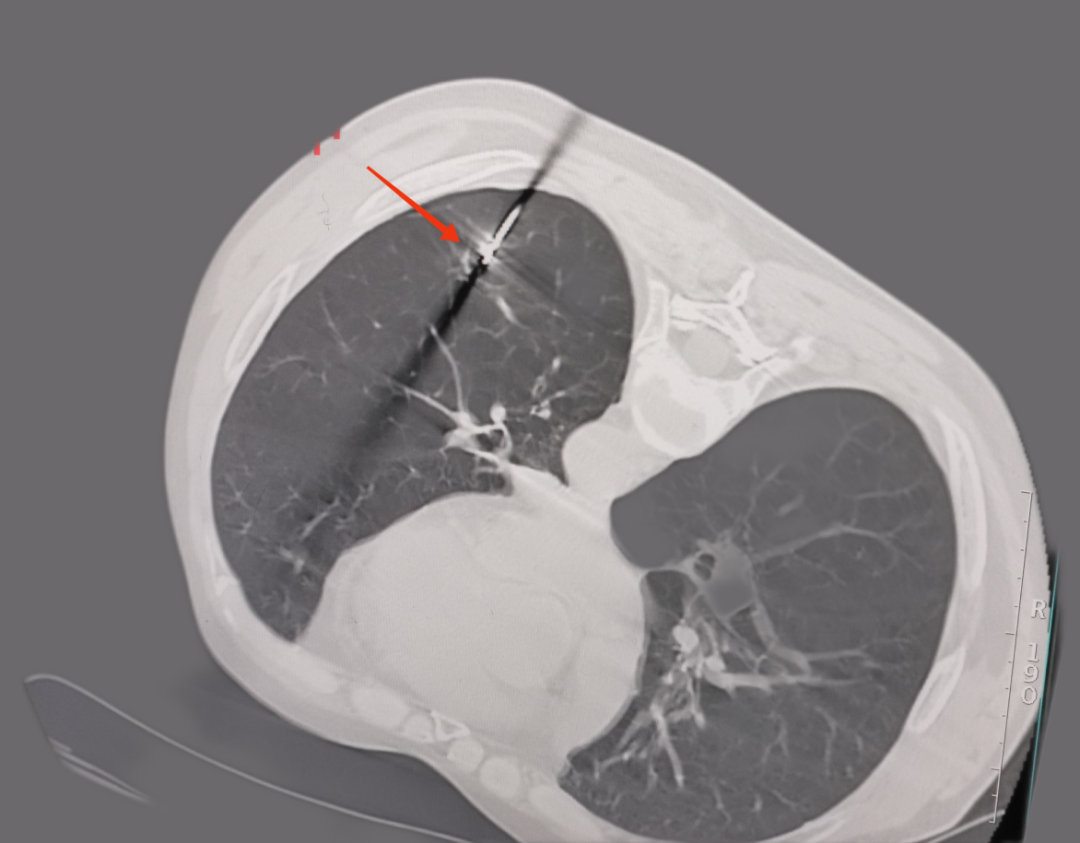

微波射頻消融手術(shù)中

微波射頻針精準(zhǔn)定位肺部結(jié)節(jié)